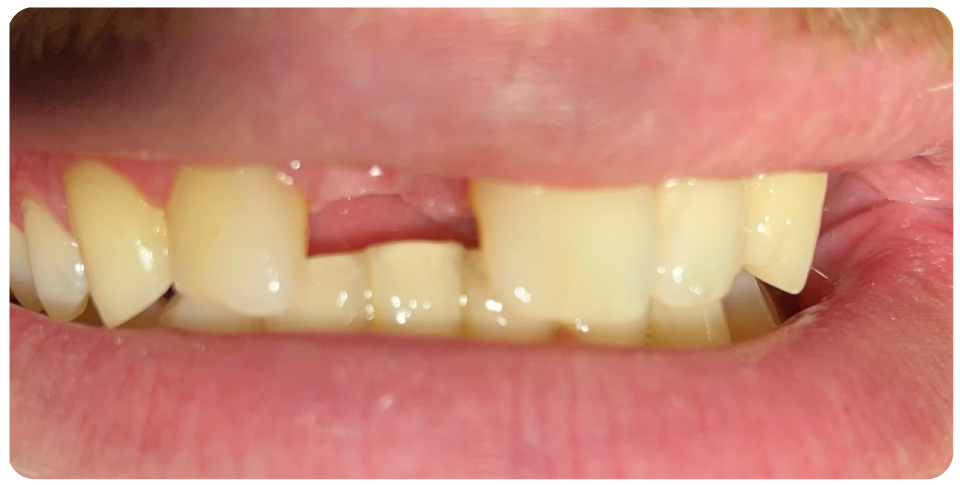

Immediate implants

Immediately after the extraction of a damaged or decayed tooth.

This approach eliminates the need for a waiting period between tooth extraction and implant placement, which is typically around 3-6 months.

Advantages – only one surgery for extraction and implant placement, early rehabilitation, preservation of bone as after extraction there is bone loss immediate implants act as a scaffold to prevent bone loss.